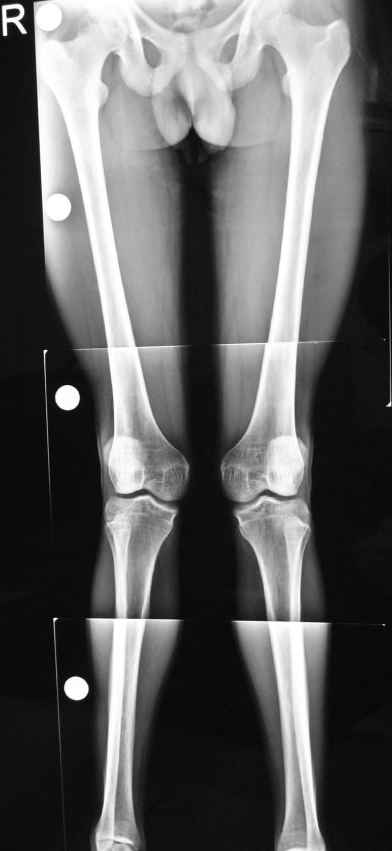

hello sirs, he is a 21 year old male short heighted thin built with failed conservative treatment tried for ? post rcketic deformity in childhood and teenage with bilateral genu valgum with intermalleolar distance 14cm and no flat foot,

the deformity is in the femur as it fully corrects on flexion of the knee his main complaint is that his knee knocks while walkingand pain in both knees while walking